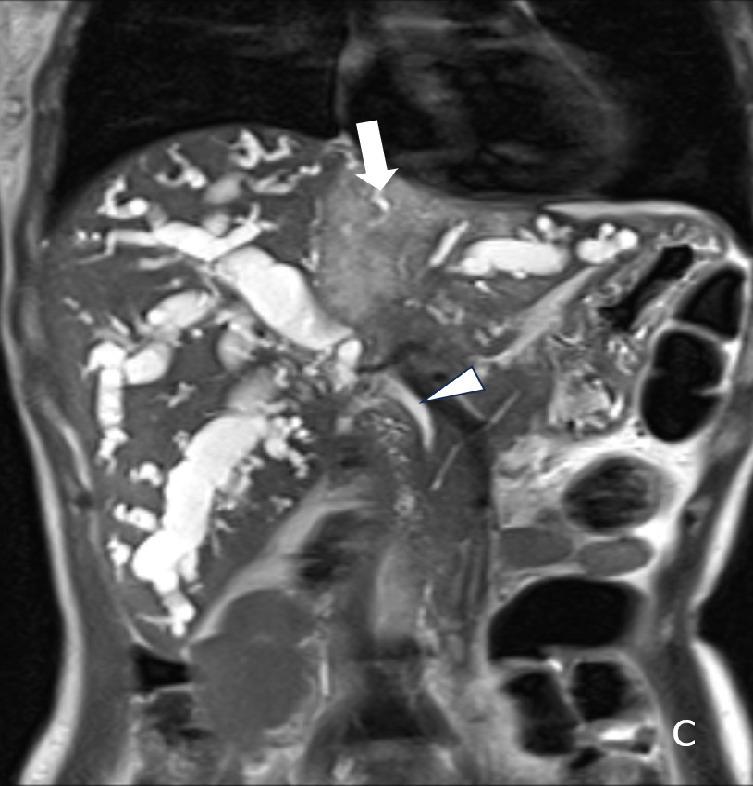

The study population was 4,337 villagers in Northern Thailand with a 5-year abdominal US surveillance. Patient demographics data and ultrasound findings of calcifications/granulomas, periductal fibrosis, and diffuse bile duct dilatation were included. A logistic regression model was used to determine significant predictors.

There were 4,225 people included with an average age of 45.49±7.66 years. Prevalence of calcifications/granulomas, periductal fibrosis, and diffuse bile duct dilatation detected on baseline sonographic surveillance was 11.7%, 20.5%, and 11.3%, respectively. The univariate analysis for significant predictors for CCA include age (Relative Risk; RR = 1.12), family history of CCA (RR = 2.29), periductal fibrosis (RR=2.38), and diffuse bile duct dilatation  (RR = 7.59). The multivariate analysis the independent predictors were age (RR = 1.12), family history of CCA (RR = 1.92), and diffuse bile duct dilatation (RR = 5.94), respectively.

The sonographic predictor for CCA surveillance in endemic areas is diffuse bile duct dilatation.  Age and family history of CCA are also helpful clinical markers.